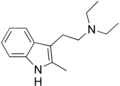

| 2-Me-DET | artificial | 2-CH3 | CH2CH3 | CH2CH3 | N,N-Diethyl-2-(2-methyl-1H-indol-3-yl)ethan-1-amine | 26628-88-6 |